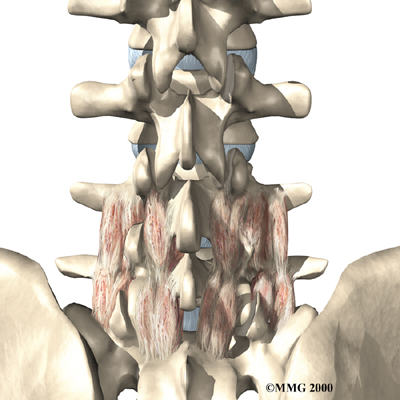

Posterior Lumbar Fusion

Lumbar disc herniation causes mechanical pain, the type of pain caused by wear and tear in the parts of the lumbar spine. Fusion surgery is mainly used to stop movement of the painful area by joining two or more vertebrae into one solid bone. This keeps the bones and joints from moving, easing mechanical pain.

In posterior lumbar fusion, the surgeon lays small grafts of bone over the problem area on the back of the spinal column. Most surgeons will also apply metal plates and screws to prevent the problem vertebrae from moving. This protects the graft so it can heal better and faster.

Related Document: FYZICAL Albany's Guide to Posterior Lumbar Fusion